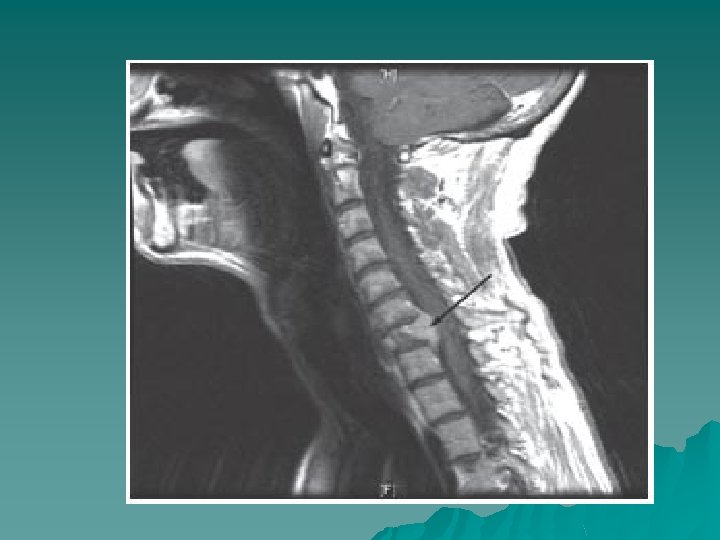

Diagnosis u In the history - especially in a known cancer patient. u MRI spine – urgent u Referral to Oncology - urgent

Aetiology 3 routes: u Vertebral mets invading the epidural space, or causing bone destruction and fragments of bone compressing the cord u Retroperitoneal tumours grow through the intervertebral foramina u Compression of blood supply to cord causing ischemia and oedema and hence loss of function